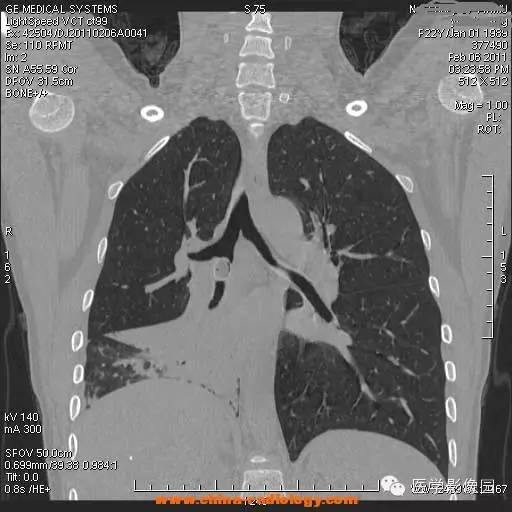

【病例】支气管异物1例CT影像表现

女,22岁,食用开心果后咳嗽不适。

管支气管异物是临床常见急症。异物可存留在喉咽腔、喉腔、气管和支气管内,引起声嘶、呼吸困难等,右支气管较粗短长,故异物易落入右主支气管。75%发生于2岁以下的儿童。CT三维重建清晰直观的显示异物的大小、位置,并能观察肺组织内是否有病变。